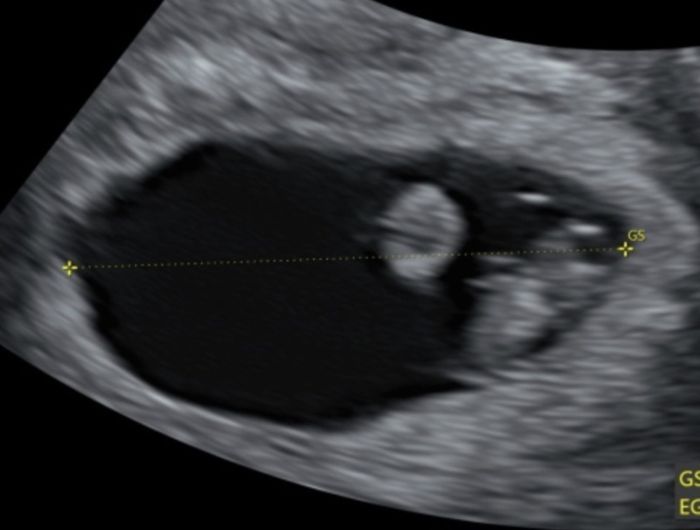

Hola! Quería preguntaros si entendéis el método Ramzi si sabéis que puede ser. Os lo agradecería muchísimo. Es una ecografía de 7 semanas

Hola. Sabrías decirme en esta transvaginal de 6+2 si es niño o niña? Gracias Smiley smileMétodo Ramzi 2